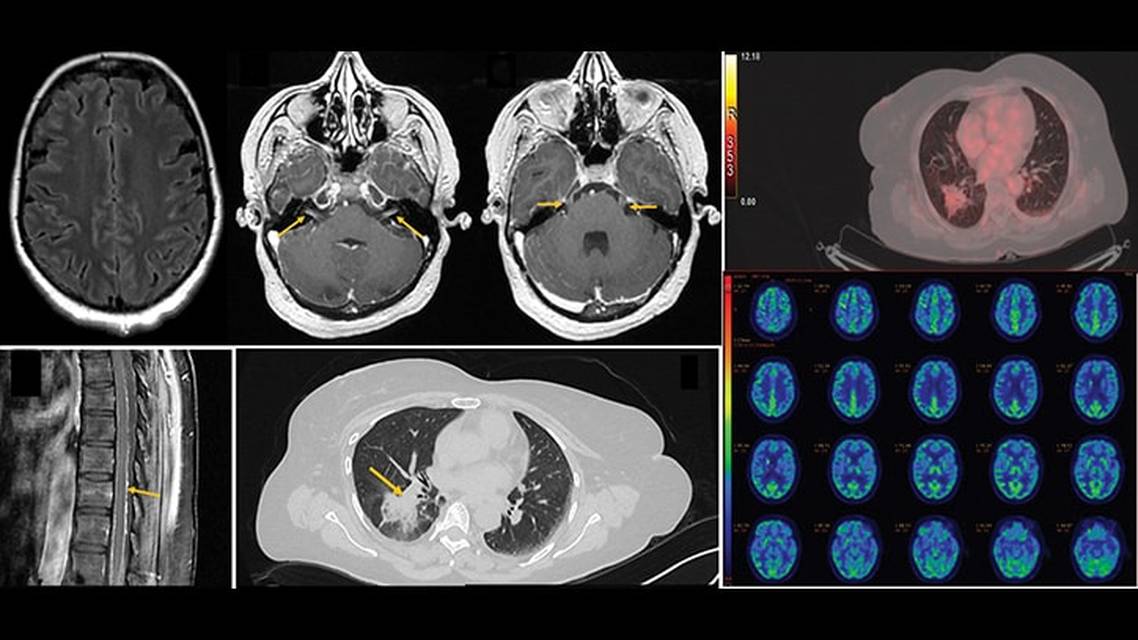

Contrast-enhanced brain and spine MRI scans repeated at our institute showed diffuse leptomeningeal enhancement with enhancement of bilateral cranial nerves V, VI, and VII (Figure 1, A–D). Hematologic and biochemical investigations, including thyroid profile, vitamin B12 levels, kidney and liver function tests, and sodium level, had normal results. Erythrocyte sedimentation rate was elevated (37 mm/h). Lumbar puncture revealed normal opening pressure (14 cm H2O), clear cerebrospinal fluid (CSF), elevated protein level (155 g/dL), reduced glucose level (53 mg/dL), and mild pleocytosis (25 cells/uL, lymphocytic predominant). Other tests, including CSF cytology for malignant cells, CSF cartridge-based nucleic acid amplification test, India ink test, cryptococcal antigen test, and galactomannan test were negative. Aerobic, fungal, and mycobacterial cultures were sterile. Contrast-enhanced CT of the thorax and abdomen showed an ill-defined consolidation in the superior segment of the right lower lobe and lateral segment of the right middle lobe with extension into segmental bronchi (Figure 1E). Bronchoscopy and bronchoalveolar lavage were negative for fungal, mycobacterial, and other infective etiology. Scrub typhus and Lyme serology tests were also negative.

![Figure 1. MRI postcontrast fluid-attenuated inversion recovery sequence shows diffuse leptomeningeal enhancement (A). Contrast enhancement is seen along bilateralcranial nerves VII , V and VI (B and C). Postcontrast T1-weighted image of the spine shows leptomeningeal enhancement along the surface of the spinal cord (D). Axial CT (lung window) of the thorax shows a lung mass with surrounding ground-glass opacities in the superior segment of the right lower lobe (E). Whole-body [¹⁸F]fluorodeoxyglucose positron emission tomography scan shows focal consolidation in the right lung lower lobe (F). Decreased metabolism is noted in bilateral frontal and parietal regions (G).](https://cdn.practicalneurology.com/cache/91/25/9125aedfafd8eb922a663b71c4858269.png)

Whole-body [¹⁸F]fluorodeoxyglucose positron emission tomography was performed and showed a metabolically active nodular opacification in the right lung (Figure 1F) as well as hypometabolism in the bilateral prefrontal and parietal regions with relative hypermetabolism in the mesial temporal lobes and cerebellum (Figure 1G). The presence of rapidly progressive dementia (RPD), focal impaired awareness seizures, behavioral changes and plateau waves, along with focal hypermetabolism in mesial temporal regions, strengthened the possibility of paraneoplastic autoimmune encephalitis. Intravenous immunoglobulin was started at 400 mg/kg of body weight daily for 5 days, but no substantial improvement in symptoms occurred. A paraneoplastic antibody panel including anti-Hu, anti-Ri, anti-CRMP5, and anti-Yo had negative results. CT-guided biopsy of the lung lesion revealed nonmucinous lung adenocarcinoma with a lepidic pattern. On immunohistochemistry, the atypical cells lining the alveolar spaces (lepidic pattern) showed nuclear positivity for thyroid transcription factor-1 (TTF-1) (Figure 2, C–E). Because a localized lung malignancy causing leptomeningeal disease without any regional spread was unusual, a repeat CSF lumbar puncture was performed to investigate for malignant cytology, but results were negative. Brain biopsy was planned, but the relatives did not consent to this test. Considering the available data, a diagnosis was made of leptomeningeal carcinomatosis causing RPD and plateau waves.